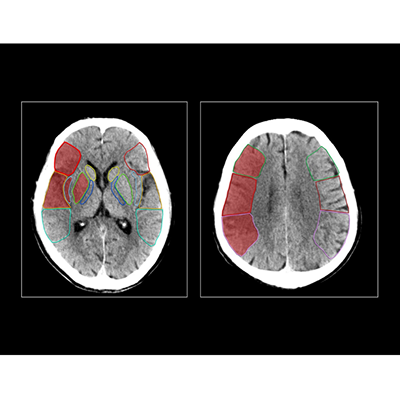

搭载该算法的联影智能CT脑缺血智能分析系统可精确分割并定位ASPECTS评分区域,自动提供左、右脑ASPECTS评分并标记早期缺血改变区域,提供ASPECTS评分预后参考指南及随访分析,帮助医生提高阅片准确度和一致性,将评分时间从几分钟缩短至几秒钟,把握治疗黄金时机。

病例展示

某三甲医院,一女性患者因突发左侧肢体无力、失语和双眼凝视等症状入院。

医生基于一站式CT扫描结果以及脑缺血AI分析,诊断该患者存在脑缺血情况,右脑ASPECTS评分为6分,有4个受影响区域。值得注意的是,该患者的豆状核和岛叶区域存在缺血问题,但由于早期征象不易识别,医生借助AI辨别发现出这两处区域的缺血情况。

而结合头颅CTP AI结果,可发现该患者右侧大脑半球异常灌注,CTA也清晰显示出患者右颈内动脉及大脑中动脉闭塞。因此,医生决定采取经皮颅内动脉取栓术。